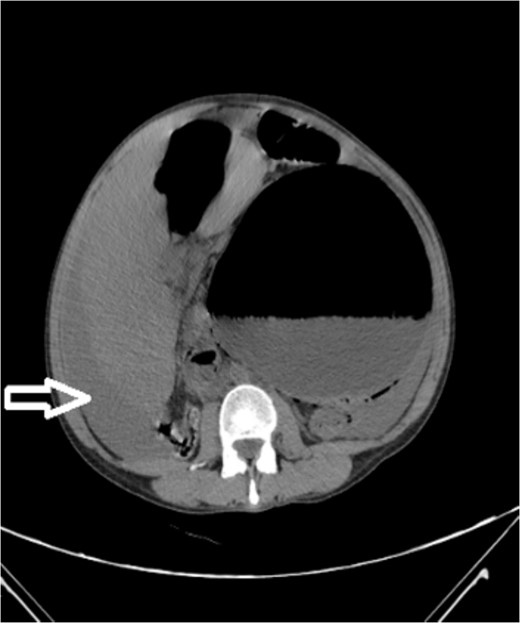

Upon admission to our hospital, the patient’s physical examination revealed hypotension (87/52 mmHg) and tachycardia (150 bpm), along with marked diffuse abdominal tenderness and guarding. Laboratory investigations indicated a hemoglobin level of 7.1 g/dl, a white blood cell count of 14.5 × 103 μl, and a platelet count of 202 × 103 μl. An abdominal CT scan without contrast showed an enlarged ectopic spleen measuring 18 cm in the right abdominal area, a distended stomach, a moderate volume of hemoperitoneum, and significant intra-abdominal fluid accumulation. CT findings are shown in Figs 1–3. Based on these findings, the patient was immediately transferred to the operating room.

Noncontrast axial CT scan of the abdomen showing a perihepatic hematoma.